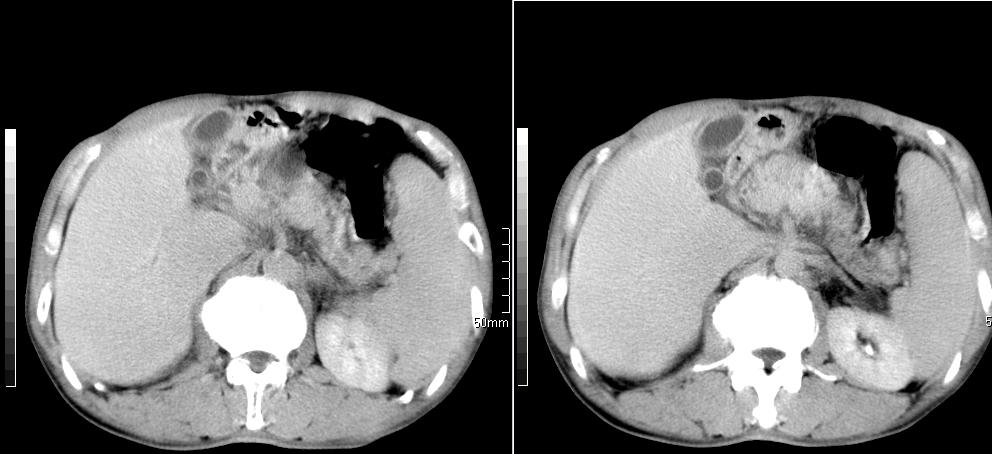

标题: CT26769:男,58岁,腹胀、腹部不适一年余 [打印本页]

标题: CT26769:男,58岁,腹胀、腹部不适一年余

肝右叶后段见小片状略低密度影,边缘不清,轻度强化,内见小血管影通过同,延迟期为等密度,考虑局灶性脂肪浸润。需与血管瘤鉴别。另有胆囊炎、脾大。

1 慢性胰腺炎并假囊肿形成。2 慢性胆囊炎并累及肝边缘!

1)考虑慢性胰腺炎并假性囊肿形成。2) 慢性胆囊炎。3)肝内胆管扩张。

1肝内胆管扩张,性质待定,2慢性胰腺炎胰管扩张,胰腺颈部假囊肿,3肝左叶低密度为小囊肿,4胆囊炎。